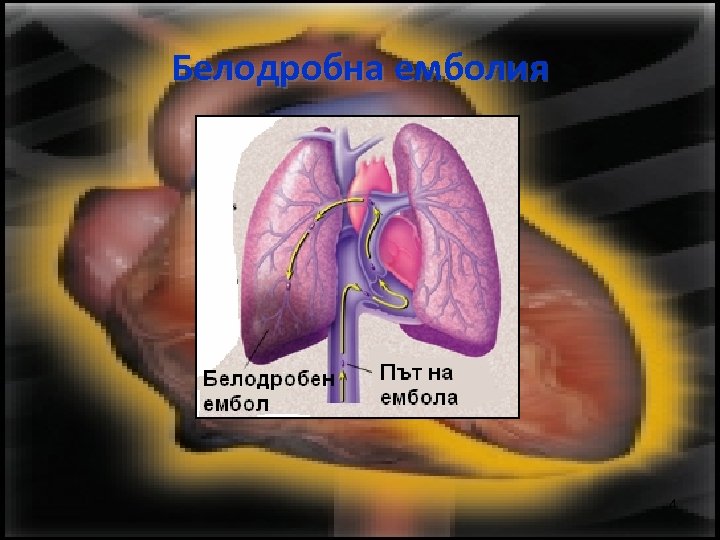

Белодробна емболия 4

Белодробна емболия • Масивен фатален белодробен емболизъм • Масивен емболизъм при хемодинамично нестабилни пациенти 5

Белодробна емболия • Белодробен емболизъм, без значими хемодинамични нарушения • Леко изразени форми, включващи малки множествени емболи, причиняващи диспнея, белодробна хипертензия и/или десностранна помпена недостатъчност. 6